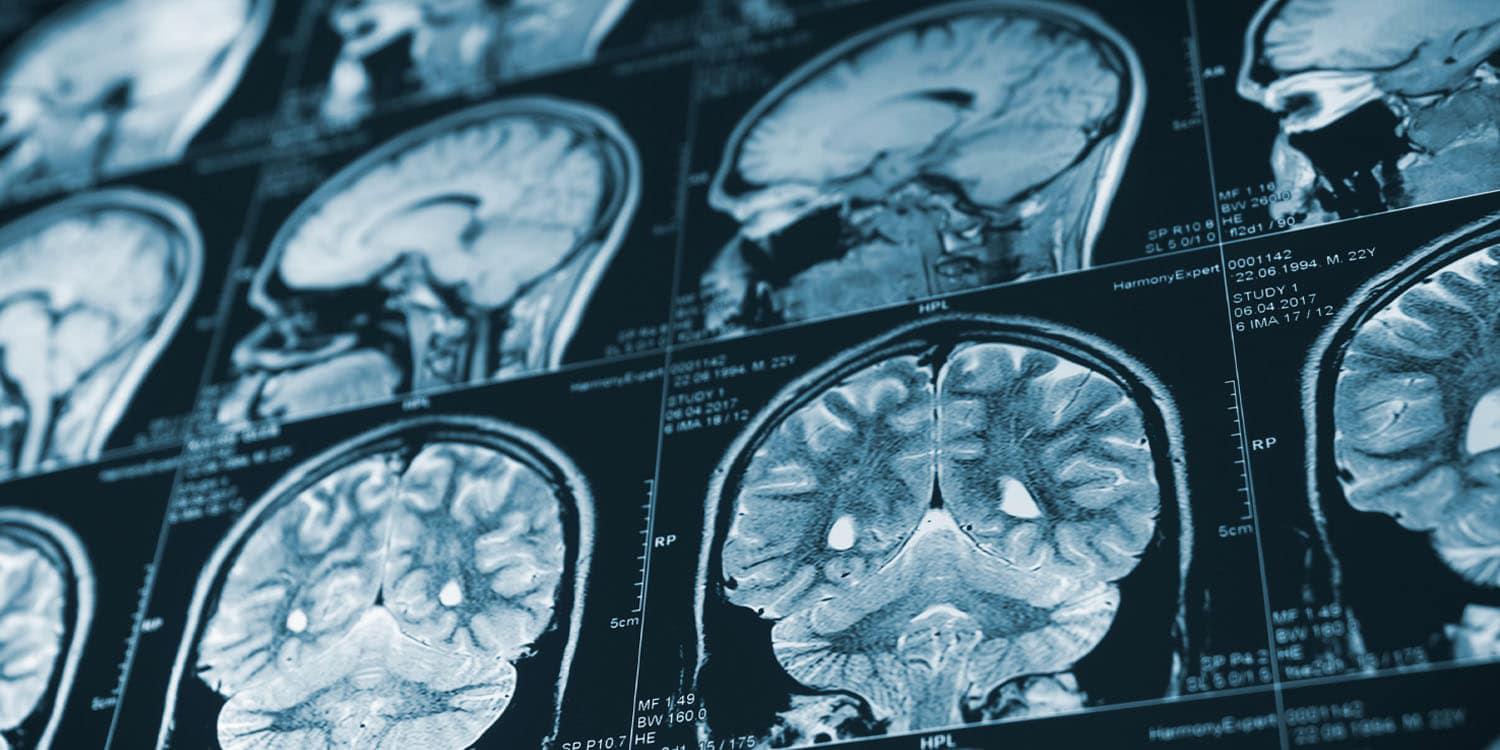

Kindheitstraumata sind mit unterschiedlichen Alterungsmustern im mittleren Lebensalter des Gehirns verbunden. Missbrauch und Vernachlässigung in der Kindheit sind mit unterschiedlichen Mustern der Veränderung des menschlichen Gehirns und Geistes verbunden, wenn Menschen älter werden.

Childhood trauma is linked to different aging patterns in the midlife brain